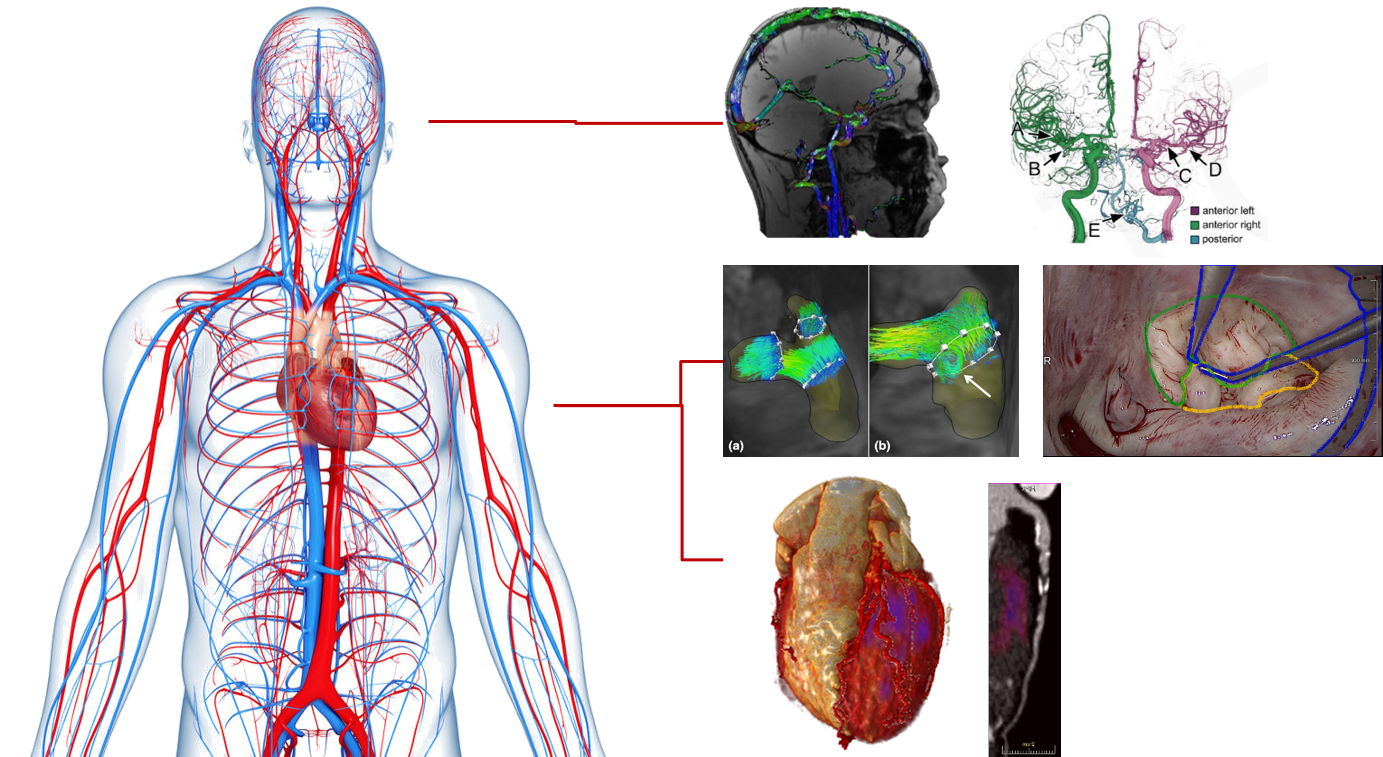

The course will introduce types and formats of medical image data (ultrasound, MRI, CT, histological images, …) with their characteristic properties and requirements for preprocessing.

Techniques for the extraction and quantification of anatomical structures as well as functional information (motion, bloodflow, perfusion) will be introduced and explored in the exercises.

- How to segment and model anatomical structures

- How to extract physiological information from 4D image data

Segmentation of tubular structures, organs and pathological tissue with tracking, methods, morphological and classification approaches such as Gaussian mixture models and Markov random fields, deformable models; time series analysis including registration, motion tracking, (model-based) change assessment; machine learning in medical image processing